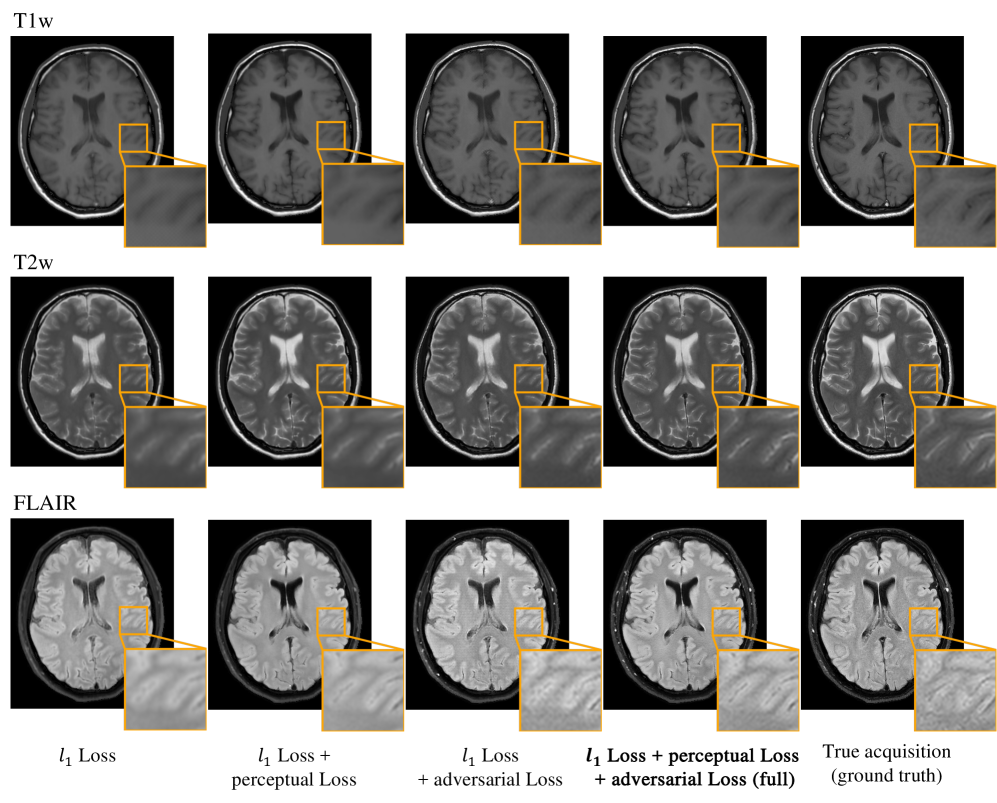

To investigate and better understand the impact of loss functions (§ 2.3) on the resulting image quality, we conducted an ablation study by comparing our overall loss function LGsubscript𝐿GL_{\mathrm{G}} (Equation 6) to L1subscript𝐿subscript1L_{\ell_{1}}, L1+λvggLvggsubscript𝐿subscript1subscript𝜆vggsubscript𝐿vggL_{\ell_{1}}+\lambda_{\mathrm{vgg}}L_{\mathrm{vgg}} and L1+λadvLadvsubscript𝐿subscript1subscript𝜆advsubscript𝐿advL_{\ell_{1}}+\lambda_{\mathrm{adv}}L_{\mathrm{adv}} losses. We trained separate models with different objective functions using the same training setup and datasets (i.e., training set, learning rate, epochs, etc.). Figure 6 shows the results on a representative 2D brain slice. The model trained with pure L1subscript𝐿subscript1L_{\ell_{1}} (left column) suffers from degraded perceptual image quality and exhibits some blurring, which is consistent with the findings in literature Wang et al. (2022); Isola et al. (2017); Wang et al. (2020). Adding perceptual VGG loss (second column) encourages finer details and sharper edges. However, blurring artifacts remain (as seen in T2w and FLAIR). Adding adversarial loss on top of L1subscript𝐿subscript1L_{\ell_{1}} (third column) encourages even finer structures but suffers from residual blurring (T2w) and recurrent checkerboard artifacts (FLAIR). By incorporating both perceptual loss and adversarial loss, the model trained with our proposed objective (fourth column, Equation 6) can further improve the synthesized image quality, reconstructing more delicate textures (T2w example) and producing more faithful contrast (See the FLAIR example).

Refer to caption

Figure 6: Representative visual comparison of N-DCSNet with different loss functions. From left to right, we compare our full objective (fourth column - Equation 6) with L1subscript𝐿subscript1L_{\ell_{1}}, L1+λvggLvggsubscript𝐿subscript1subscript𝜆vggsubscript𝐿vggL_{\ell_{1}}+\lambda_{\mathrm{vgg}}L_{\mathrm{vgg}}, L1+λadvLadvsubscript𝐿subscript1subscript𝜆advsubscript𝐿advL_{\ell_{1}}+\lambda_{\mathrm{adv}}L_{\mathrm{adv}} and the ground truth. Perceptual VGG loss encourages sharper edges compared to pure L1subscript𝐿subscript1L_{\ell_{1}}, while adversarial loss further improves the image quality. The model trained with our full objective is able to recover subtle structures and show better visual agreements with the ground truth.

Table 3 summarizes the five evaluation metrics for N-DCSNet trained with different loss functions. Since the model trained with pure L1subscript𝐿subscript1L_{\ell_{1}} loss optimizes the pixel distances, it produces the best nRMSE and PSNR results. However, it is known that nRMSE and PSNR do not match human perception Zhang et al. (2018). For perception-representative metrics (SSIM, LPIPS, FID), N-DCSNet trained with our proposed full objective outperforms the other loss functions for all three contrasts (except SSIM for T1w), which demonstrates the effectiveness of our loss functions in producing high-fidelity contrast-weighted images.